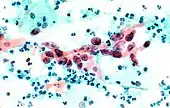

The stain should result in cells that are fairly transparent so even thicker specimens with overlapping cells can be interpreted.[2] Cell nuclei should be crisp, blue to black on color[12][13] and the chromatin patterns of the nucleus should be well defined. Cell cytoplasm stains blue-green and keratin stains orange in color.[13][5]

Eosin Y stains the superficial epithelial squamous cells, nucleoli, cilia, and red blood cells.[2] Light Green SF yellowish stains the cytoplasm of other cells, other than superficial squamous cells.[2] Superficial cells are orange to pink, and intermediate and parabasal cells are turquoise green to blue.[12]

Benign urine cytology sample.

Squamous cell carcinoma in the cervix.